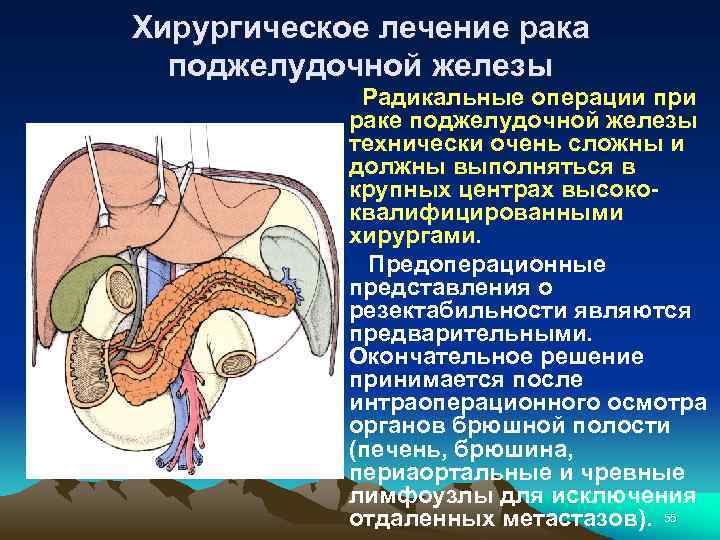

Хирургическое лечение рака поджелудочной железы Радикальные операции при раке поджелудочной железы технически очень сложны и должны выполняться в крупных центрах высококвалифицированными хирургами. Предоперационные представления о резектабильности являются предварительными. Окончательное решение принимается после интраоперационного осмотра органов брюшной полости (печень, брюшина, периаортальные и чревные лимфоузлы для исключения отдаленных метастазов). 55